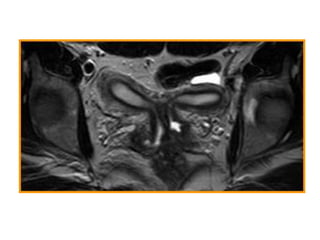

Agenesia e Hipoplasia

 5-10 %

 Fallo temprano en el desarrollo embrionario

 El Síndrome de Mayer-Rokitansky es la

malformación clase I más frecuente.

 Agenesia vaginal completa

 Agenesia uterina en el 90% de los casos

 Útero rudimentario en el 10% restante

 Se presenta con amenorrea en pacientes con

características sexuales secundarias

presentes, pues la función ovárica es normal

AGENESIA VAGINAL